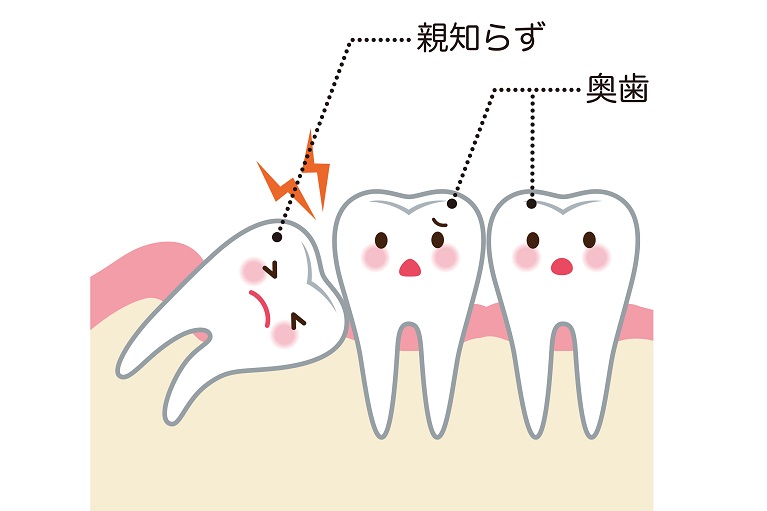

親知らずの抜歯

抜く/抜かないの見極めが重要な親知らず。

抜く/抜かないの見極めが重要な親知らず。

痛みや腫れがあるときはもちろん、症状がなくても早めの検査・診断を受けておくことをお勧めします。